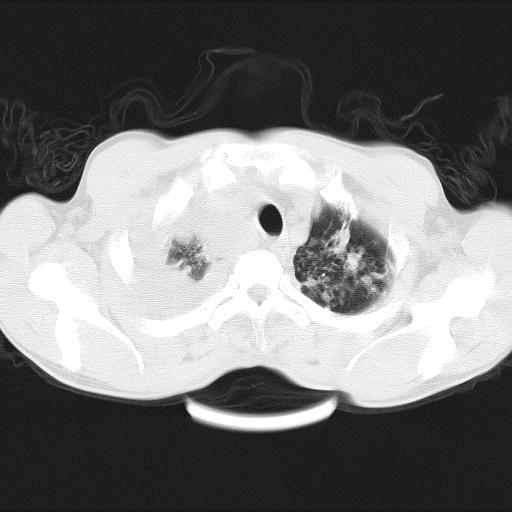

男性,44岁,结核病史多年。现胸闷气短,咳嗽,偶咳血。

双肺多发结节影最分空洞形成考虑占位不除外结核

1、右侧大量胸腔积液伴右肺压缩性膨胀不全,建议抽液治疗后复查 2、两肺继发性tb伴空洞形成。

1)两肺继发性肺结核伴空洞形成,左肺多发性结核球。2)右侧大量胸腔积液伴右肺部分膨胀不全。3)纵隔淋巴结肿大。

吉大一院胸水抽检结果:结核性胸水